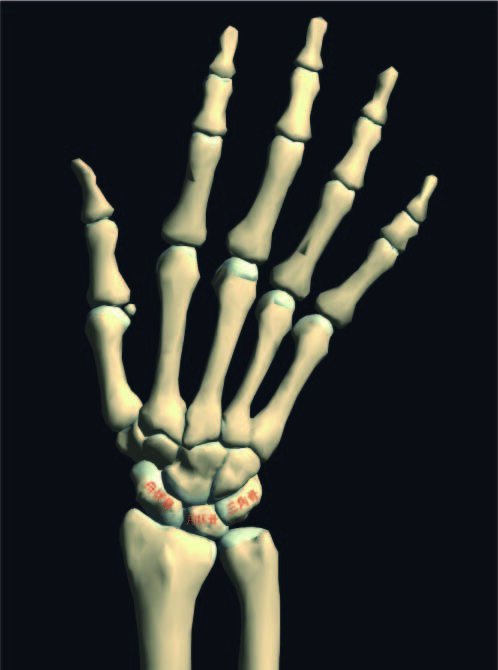

レントゲンの結果は「三角骨骨折」

手首の手根骨、小指側の骨の骨折ですね。

舟状骨、月状骨の骨折は多々ありますが、

三角骨の骨折は珍しいタイプでございます。